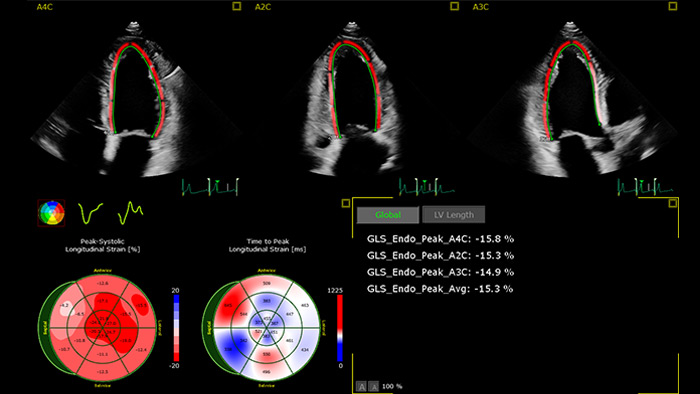

Skuteczne przeciwdziałanie kardiotoksyczności leków przeciwrakowych wymaga współpracy pomiędzy specjalistami kardiologami a onkologami. W idealnych warunkach pacjent, który ma otrzymać potencjalnie kardiotoksyczny lek, powinien przejść wstępną ocenę funkcji serca4. Należy jednak pamiętać, że proste i szeroko dostępne dwuwymiarowe badanie echokardiograficzne frakcji wyrzutowej lewej komory (LVEF) często nie pozwala na wykrycie drobnych zmian w jej kurczliwości. Bardziej dokładne pomiary zapewnia echokardiografia 3D, jednak dopiero pomiar globalnego odkształcenia wzdłużnego (GLS), który umożliwia przeprowadzenie analizy, pozwala w optymalny sposób wykryć na wczesnym etapie subkliniczne zaburzenia pracy lewej komory4.

Automatyczny pomiar GLS możliwy do wykonania podczas rutynowych badań

Aplikacja AutoStrain — dostępna w ultrasonografie lub stacji roboczej na potrzeby post-processingu — zapewnia szybki i prosty pomiar GLS dzięki funkcjom Auto View Recognition i Auto Contour Placement. „Wyszkolona” na ponad 6000 obrazów zapewnia uzyskiwanie wiarygodnych i powtarzalnych pomiarów odkształcenia lewej komory, które można wykonywać także w trakcie rutynowych badań.